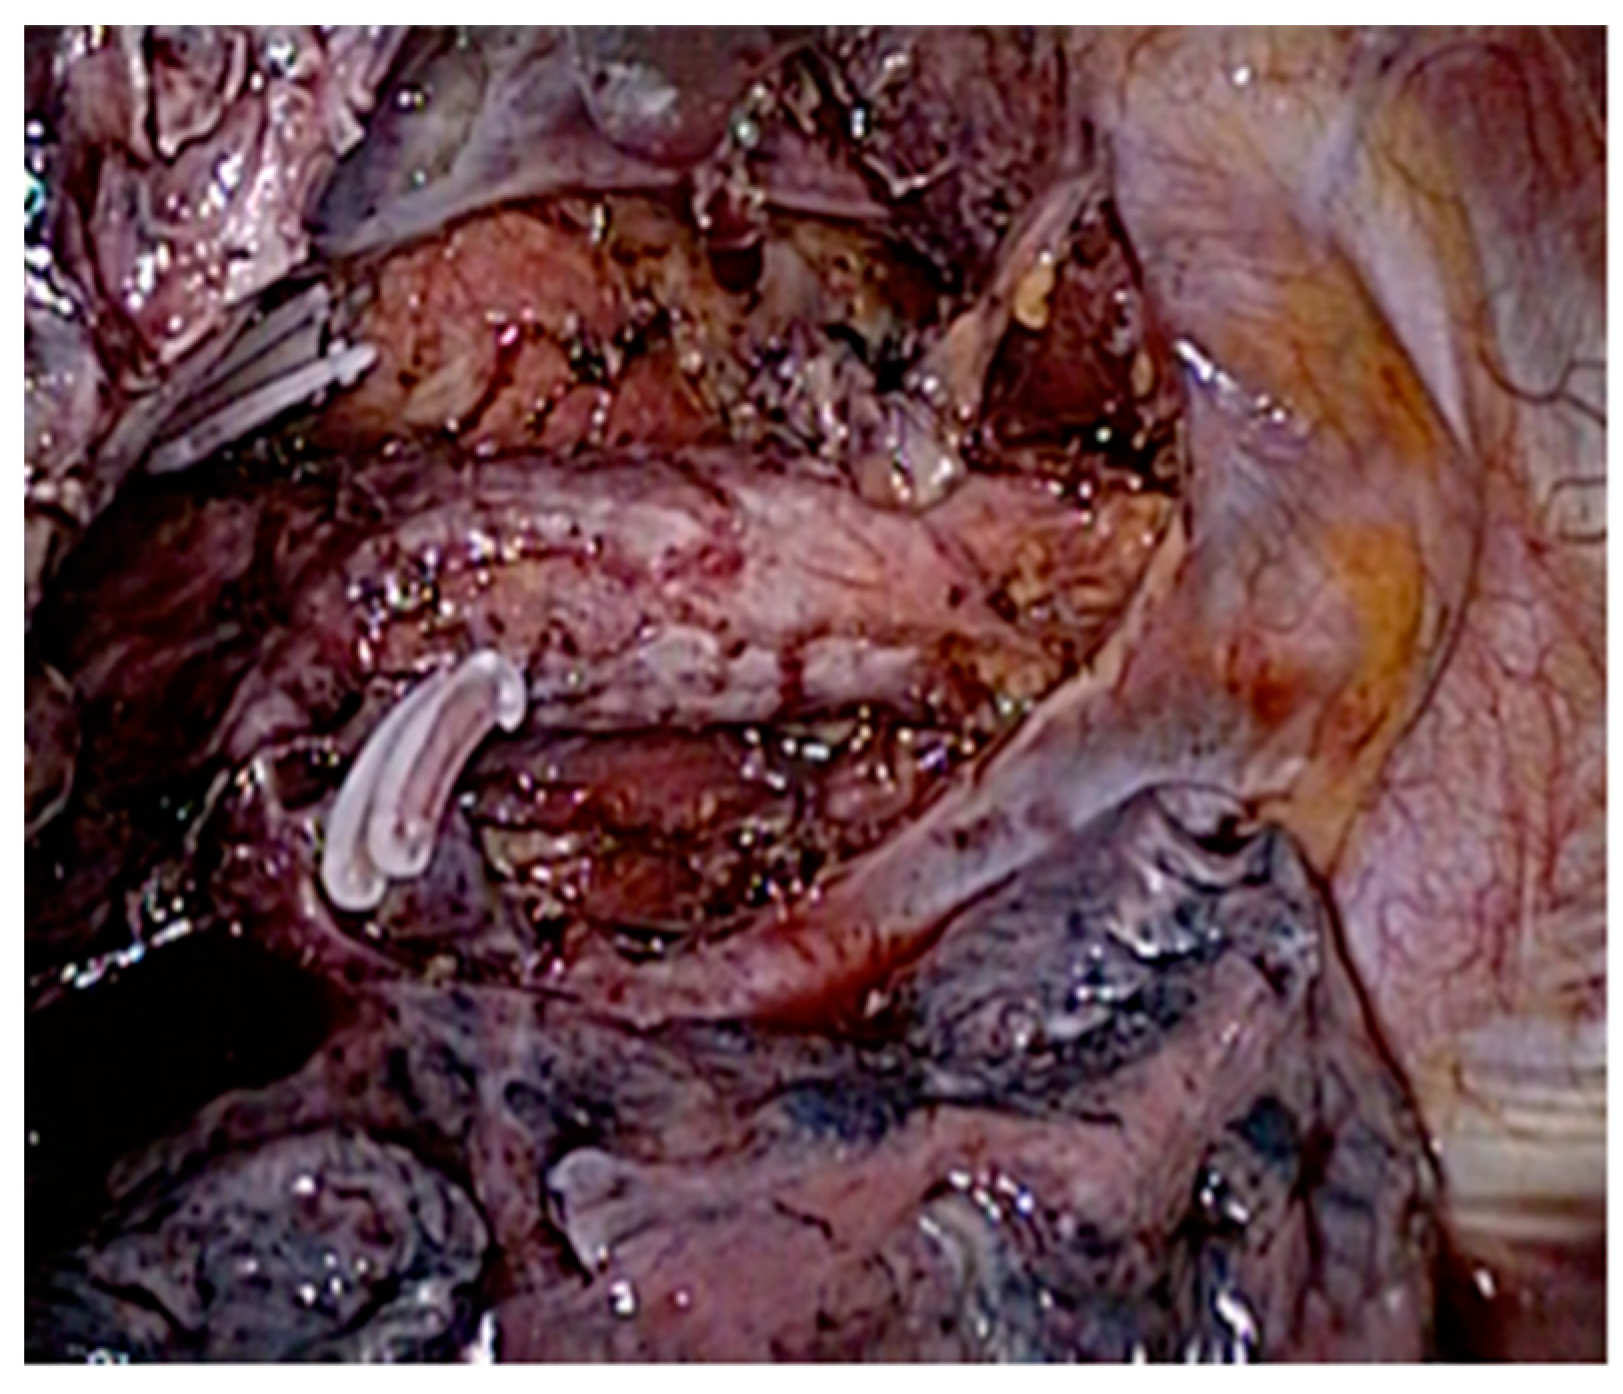

This procedure stands for a laparoscopic abdominal phase followed by a thoracic phase utilizing a prone position thoracoscopy. The abdominal phase includes laparoscopic gastric mobilization and D2 lymphadenectomy (Figure 1) and construction of the gastric conduit. D2 abdominal lymphadenectomy includes lymph node dissection of the right gastric, left gastric, common hepatic, hepato-duodenal ligament, proximal splenic-artery, celiac trunk, right- and left-paracardial, infra-diaphragmatic, and diaphragmatic hiatus nodes. Following that, the patient is turned into a prone position, and the thoracic esophagus is dissected up to the level of the azygos arch. Standard thoracic lymph node dissection includes all the subcarinal nodes, left- and right-bronchial nodes, lower-posterior mediastinum nodes, para-aortic nodes, and para-esophageal nodes (Figure 2). An intrathoracic, hand-sewn esophagogastric anastomosis was performed in two layers thoracoscopically with all patients in the prone position.

Right paratracheal nodes and nodes around the right recurrent laryngeal nerve were dissected. The proximal part of the thoracic esophagus is further mobilized cranially on its left-anterior side; an ample window is made after meticulous dissection of the space lying between the upper thoracic esophagus and trachea wall. With careful dissection, the left-recurrent laryngeal nerve was identified at the tracheoesophageal groove. Dissection of the infra-aortic and left tracheobronchial nodes is then performed. All of the lymphovascular tissues between the trachea and the left-recurrent laryngeal nerve were sharply dissected alongside the trachea and the left bronchus, in order to mark the upper border of dissection at the level of the thoracic inlet, completing thus the lymph node dissection along the left-recurrent laryngeal nerve (Figure 3, Figure 4 and Figure 5) (Video S1).

Figure 3. Superior mediastinal lymph node clearance (total).